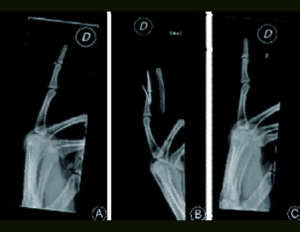

homodigital island transfer

Distal interphalangeal joint to proximal interphalangeal joint homodigital island transfer…